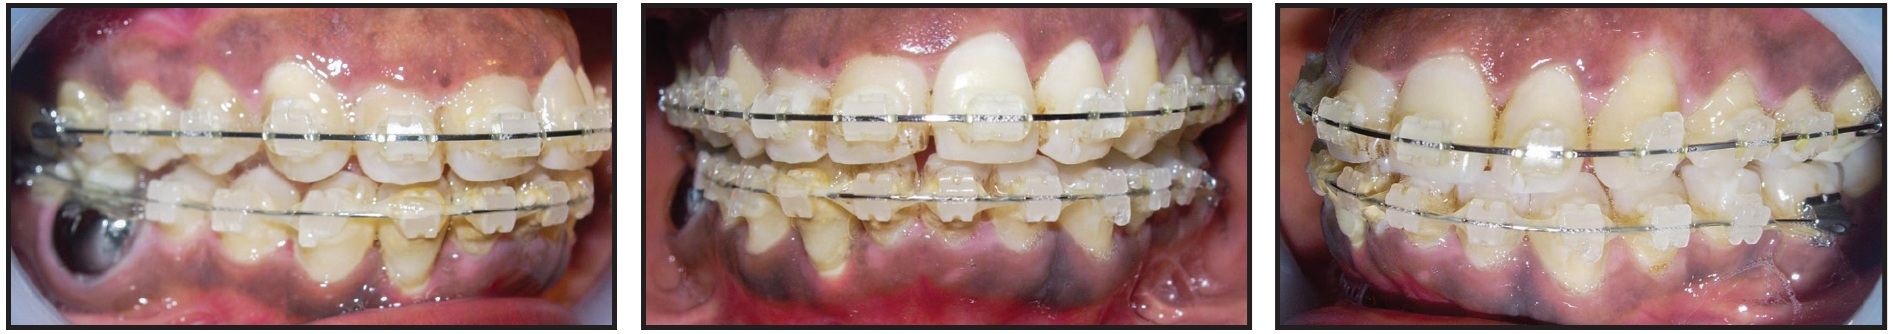

After an initial phase of dental scaling and polishing, orthodontic treatment began with .022" Roth-prescription brackets in both arches (Fig. 2).

Fig. 2 Initial bracket placement, with glass-ionomer-cement bite plane bonded to occlusal surfaces of upper first molars to unlock traumatogenic occlusion.

To unlock the occlusion, glass-ionomer-cement bite planes were bonded to the occlusal surfaces of the upper first molars. The archwire series consisted of flexible .016", .018", and .020" round coaxial wires, followed by preformed .016" and .018" round stainless steel wires. After five months of treatment, the mobility of the lower right lateral incisor persisted, despite the elimination of the traumatic occlusion (Fig. 3). Periodontal probing of the tooth's labial root surface revealed EIRR, which was confirmed with an occlusal radiograph (Fig. 4).

Fig. 3 Patient after five months of treatment, showing relief of traumatic occlusion and improved alignment.